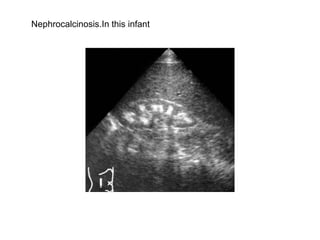

Nephrocalcinosis.In this infant

Nephrocalcinosis.Early nephrocalcinosis  causes an echo dense rim around the pyramids.